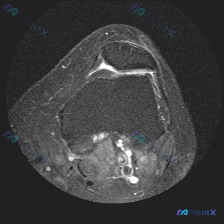

看到这个踝关节MRI的读片资料,整理了完整的分析思路分享给大家。 病例影像基本信息 这是一张踝关节冠状位T2加权MRI,核心发现是距骨穹窿外侧的软骨异常,先把影像观察结果整理清楚: 1. 骨骼系统:胫骨、腓骨、距骨骨皮质连续,没有骨折或骨质破坏;但距骨穹窿外侧可见片状T2高信号,提示局部骨髓水肿 2...